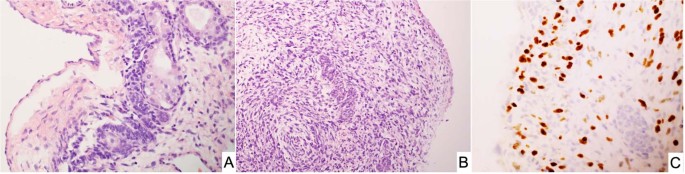

SLCT represents less than 1% of all primary ovarian tumors and is seen in a broad age range from infancy into the later adult years, but approximately 75% of cases present in women less than 30-years of age54. It was appreciated over 50 years ago that there was of an apparent association between the SLCT, multinodular goiter and cERMS54,55,56,57,58. In a cohort of 64 cases of intermediate and poorly differentiated SLCT, three patients had a history of a thyroid nodule or goiter55. Young and Scully also noted that two patients had a cERMS and four others had a thyroid “abnormality” in their study of ovarian SLCTs, to suggest that this association was more common in those women with an intermediate and poorly-differentiated SLCTs54. Once the linkage of DICER1 and familial PPB cases was reported in 20099, subsequent studies documented the linkage of DICER1 with SLCT as well as with FOXL245. Pathologically, most SLCTs in the DICER1 setting have been moderately (intermediate) or poorly differentiated tumors (Fig. 7A, B); some of these neoplasms have had heterologous elements including nodules of cartilage and rhabdomyosarcoma; the latter combination of patterns has been observed in SLCT in addition to PPB as already noted and in other DICER1-associated tumors (Fig. 8A–C)23,59. The SLCT may have a localized multicystic pattern with more than a passing resemblance to type I PPB.

A A cystic focus showing a group of Sertoli cells beneath a low cuboidal epithelial surface. B Nests of Sertoli cells surrounded by malignant-appearing, primitive-appearing spindle and round cells in another cystic area of the tumor. C MyoD immunostaining showing intense nuclear positivity to corroborate heterologous rhabdomyosarcoma.